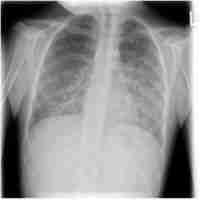

| Abstract | Background Immune reconstitution inflammatory syndrome (IRIS) refers to the phenomenon of intense immune responses against pathogens in patients with AIDS undergoing antiretroviral therapy to reconstitute immune function, resulting in functional impairment of multiple organs. Non-AIDS immunosuppressed hosts may also develop similar manifestations to IRIS during immune recovery. Case presentation An 8-year-old girl presented with acute lymphoblastic leukaemia was admitted for scheduled chemotherapy treatment. During chemotherapy, she experienced pancytopenia and Pneumocystis jirovecii pneumonia, which was diagnosed based on the abnormal shadows observed on chest computed tomography, the elevation of serum β-D-glucan, and the positive mNGS results of Pneumocystis jirovecii in both sputum and blood. After treatment with Granulocyte Colony-Stimulating Factor, sulfamethoxazole, and caspofungin, aggravation of lung lesions was discovered and severe interstitial lung disease developed in a short period along with a rapidly increasing leukocyte count. Intravenous methylprednisolone pulse therapy was given, but lung function did not improve, and she finally died after the withdrawal of medical care. Conclusions For patients with acute lymphocytic leukaemia infected with Pneumocystis jirovecii, the rapid aggravation of pulmonary lesions in the process of blood recovery and immune reconstitution should raise vigilance against the possibility of IRIS-like reactions. The use of granulocyte stimulating factors may aggravate the inflammatory response in the lungs. The timing, dosage, and duration of treatment of glucocorticoids and the impact of high-dose methylprednisolone pulse therapy on the prognosis of patients should be explored in further research. |